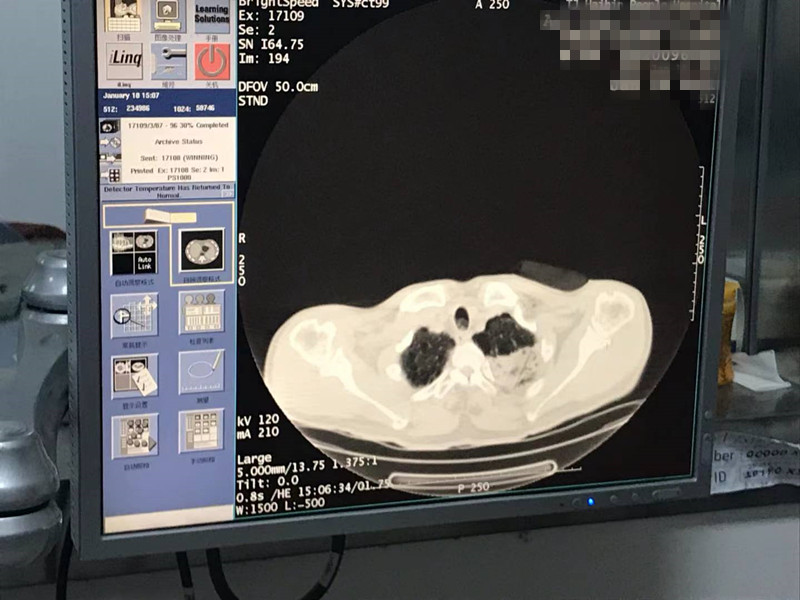

2021年1月份肺部氩氦刀手术

发布人:美国氩氦刀技术官方网站    发布时间:2021/9/22 15:39:30